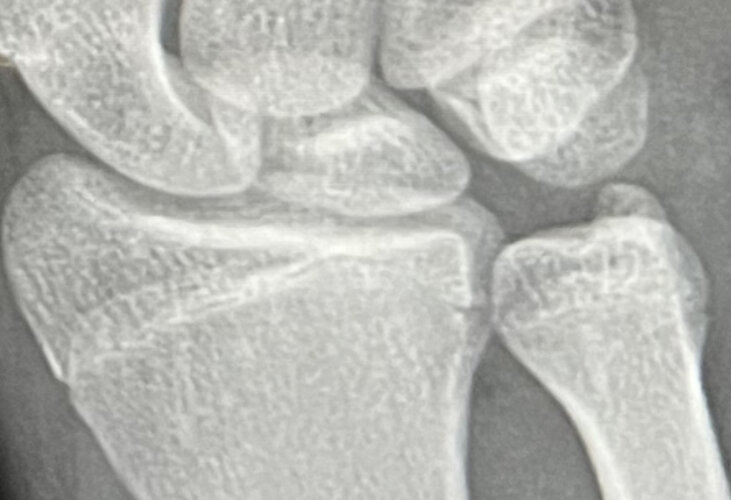

my homie has decided to blast HGH and 2mg arimidex for a year max to see if he can gain 2 inches with a bone age of 17. He’s on his moms T4 right now only, + natural AIs. gonna be getting him some Hgh just to see if this is possible. his knees and spine should be a bit younger than this wrist xray. @Lux said he had a wrist xray that was more aged than this. this is gonna be revolutionary if this is legit. i have him starting with 7IUS a day